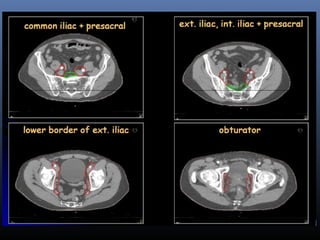

 Lenfatik metastaz:

obturator >> common iliak, presakral, paraaortik

ERT

pelvik

alan